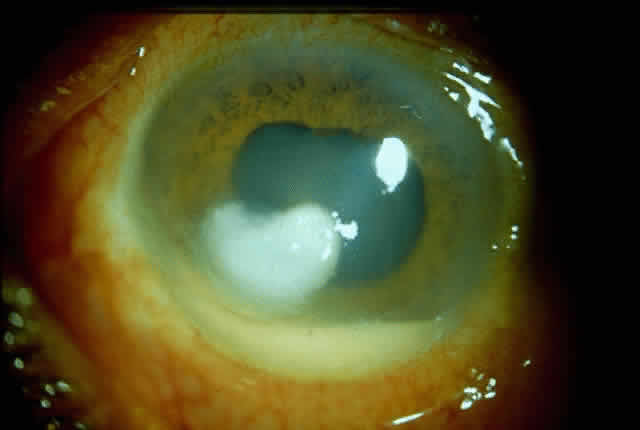

Fungal keratitis is as frequently seen as bacterial keratitis. Aspergillus and Fusarium are the two most commonly isolated organisms. Predisposing factors include trauma, foreign body, and injudicious usage of topical steroids or other indigenous medications.

Delay in diagnosis, the relative ineffectiveness of antifungal agents in most parts of the world, and the nonavailability of these drugs hinder prevention and management (Fig. 3).

Fig. 3. Advanced stage of corneal ulcer caused by Fusarium solani.